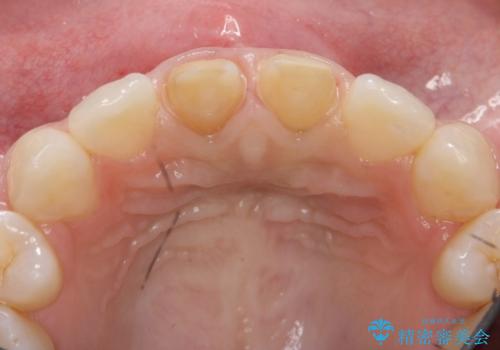

- 神経のない前歯が変色していたため、矯正治療後にセラミックで修復しました。

セラミックの前に、全体をオフィスホワイトニング(エクセレント)して周りの歯を白くして色をなじませました。

- 38万円(上顎両側1:ジルコニアクラウン スタンダード 10万円x2、ファイバーコア 2万円x2、 精密根管治療(再治療)9万円x1、仮歯 1万円x2)、ホワイトニング(エクセレント)3万円費用は治療当時の料金となります